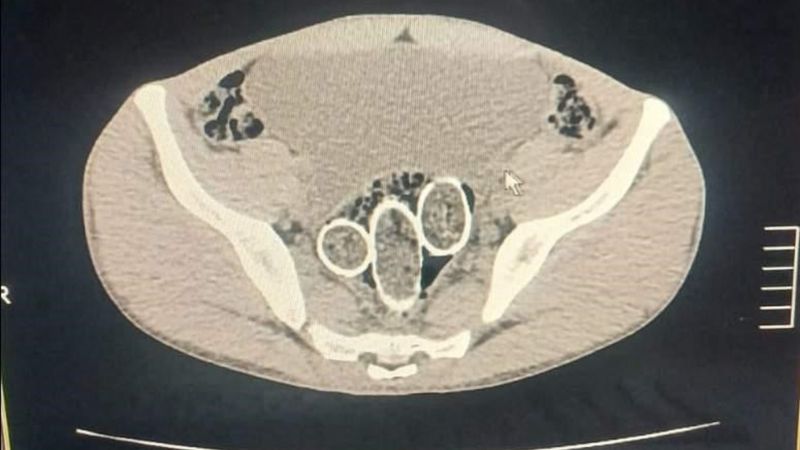

Gözaltına alınan iki şahsın iç beden muayenesinde ve kullandıkları iki araçta yapılan incelemelerde, rahimde ve midede uyuşturucu madde tespit edildi.